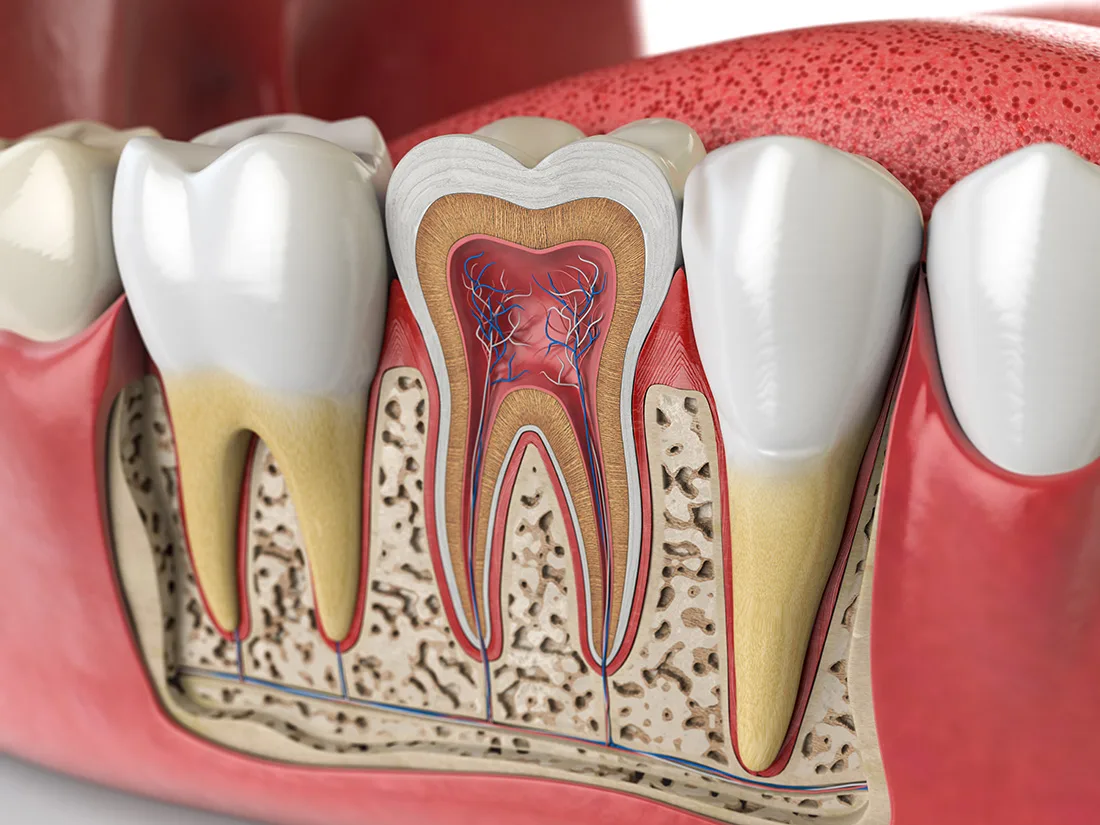

The Root Canal Treatment Process

Diagnostics & Preparation

Your dentist will begin with a comprehensive examination of your tooth and x-rays to identify the cause of your dental discomfort. If an infection is present, they'll assess its severity to determine if a root canal is the appropriate treatment option.If root canal therapy is necessary, your dentist will ensure the treatment area is completely numb, including the nerves. Before starting the procedure, they'll discuss various sedation options with you to ensure your comfort throughout the treatment.

Removing Decay & Infected Pulp

Once you're fully numbed and comfortable, your dentist will begin the process of removing decayed or infected material. They'll start from the outermost layer of enamel and work their way towards the inner pulp. After removing the infected pulp, the canals will be thoroughly cleaned and flushed with a specialized disinfectant to eliminate any remaining infection.

Filling & Sealing

After cleaning and disinfecting your tooth, your dentist will fill the inner cavity with a rubbery substance called "gutta-percha". This inert material provides support to the tooth and replaces the extracted pulp. Following this, your dentist will determine whether to restore the tooth with a filling or a dental crown. This decision is based on the extent of decay and the amount of healthy enamel remaining on the tooth.